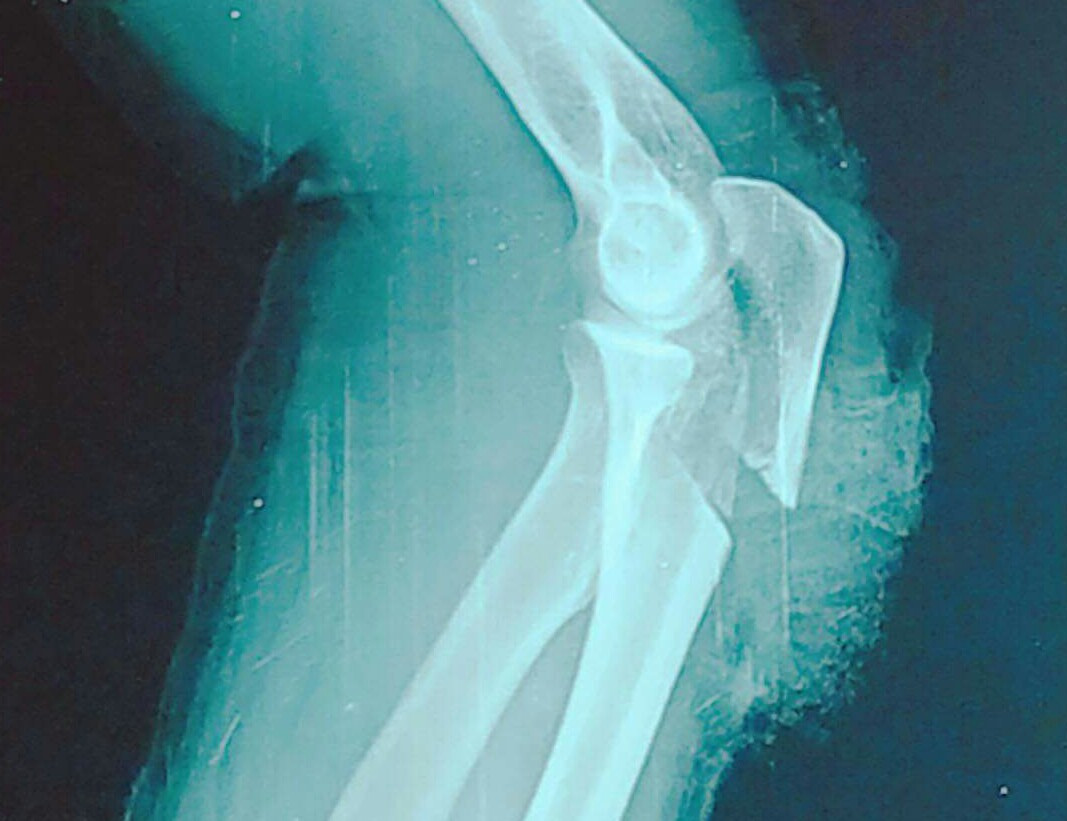

Đang ăn cơm bị kẻ lạ mặt xông vào nhà chém gần lìa cánh tay ảnh 1Cánh tay bị đứt gần lìa

Sau khi ra tay, hung thủ nhanh chóng rời đi. Hai nạn nhân bị thương nặng phải nhập viện cấp cứu, trong đó một người bị đứt gần lìa cánh tay.